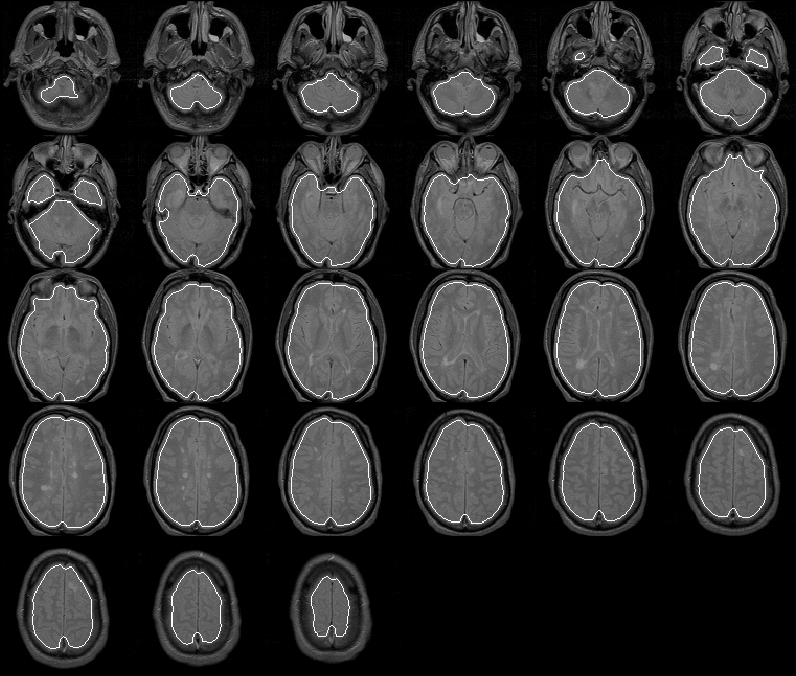

8.4.2 Data Set 2

As shown in Figure 8.13, the Generate Initial Brain Mask produces an initial brain mask for Data Set 2 that is comparable to that produced for Data Set 1. The brain mask provides a good seed for the Generate Final Brain Mask process.

Figure 8.13: The initial brain mask for MRI Data Set 2 overlaid on the PD-weighted scan.

8.4.3 Data Set 3

For Data Set 3 the Generate Initial Brain Mask process again produces a good initial brain mask to use as a seed for the Generate Final Brain Mask process. The mask is overlaid on the PD-weighted scan of Data Set 3 in Figure 8.14.

Figure 8.14: The initial brain mask for MRI Data Set 3 overlaid on the PD-weighted scan.